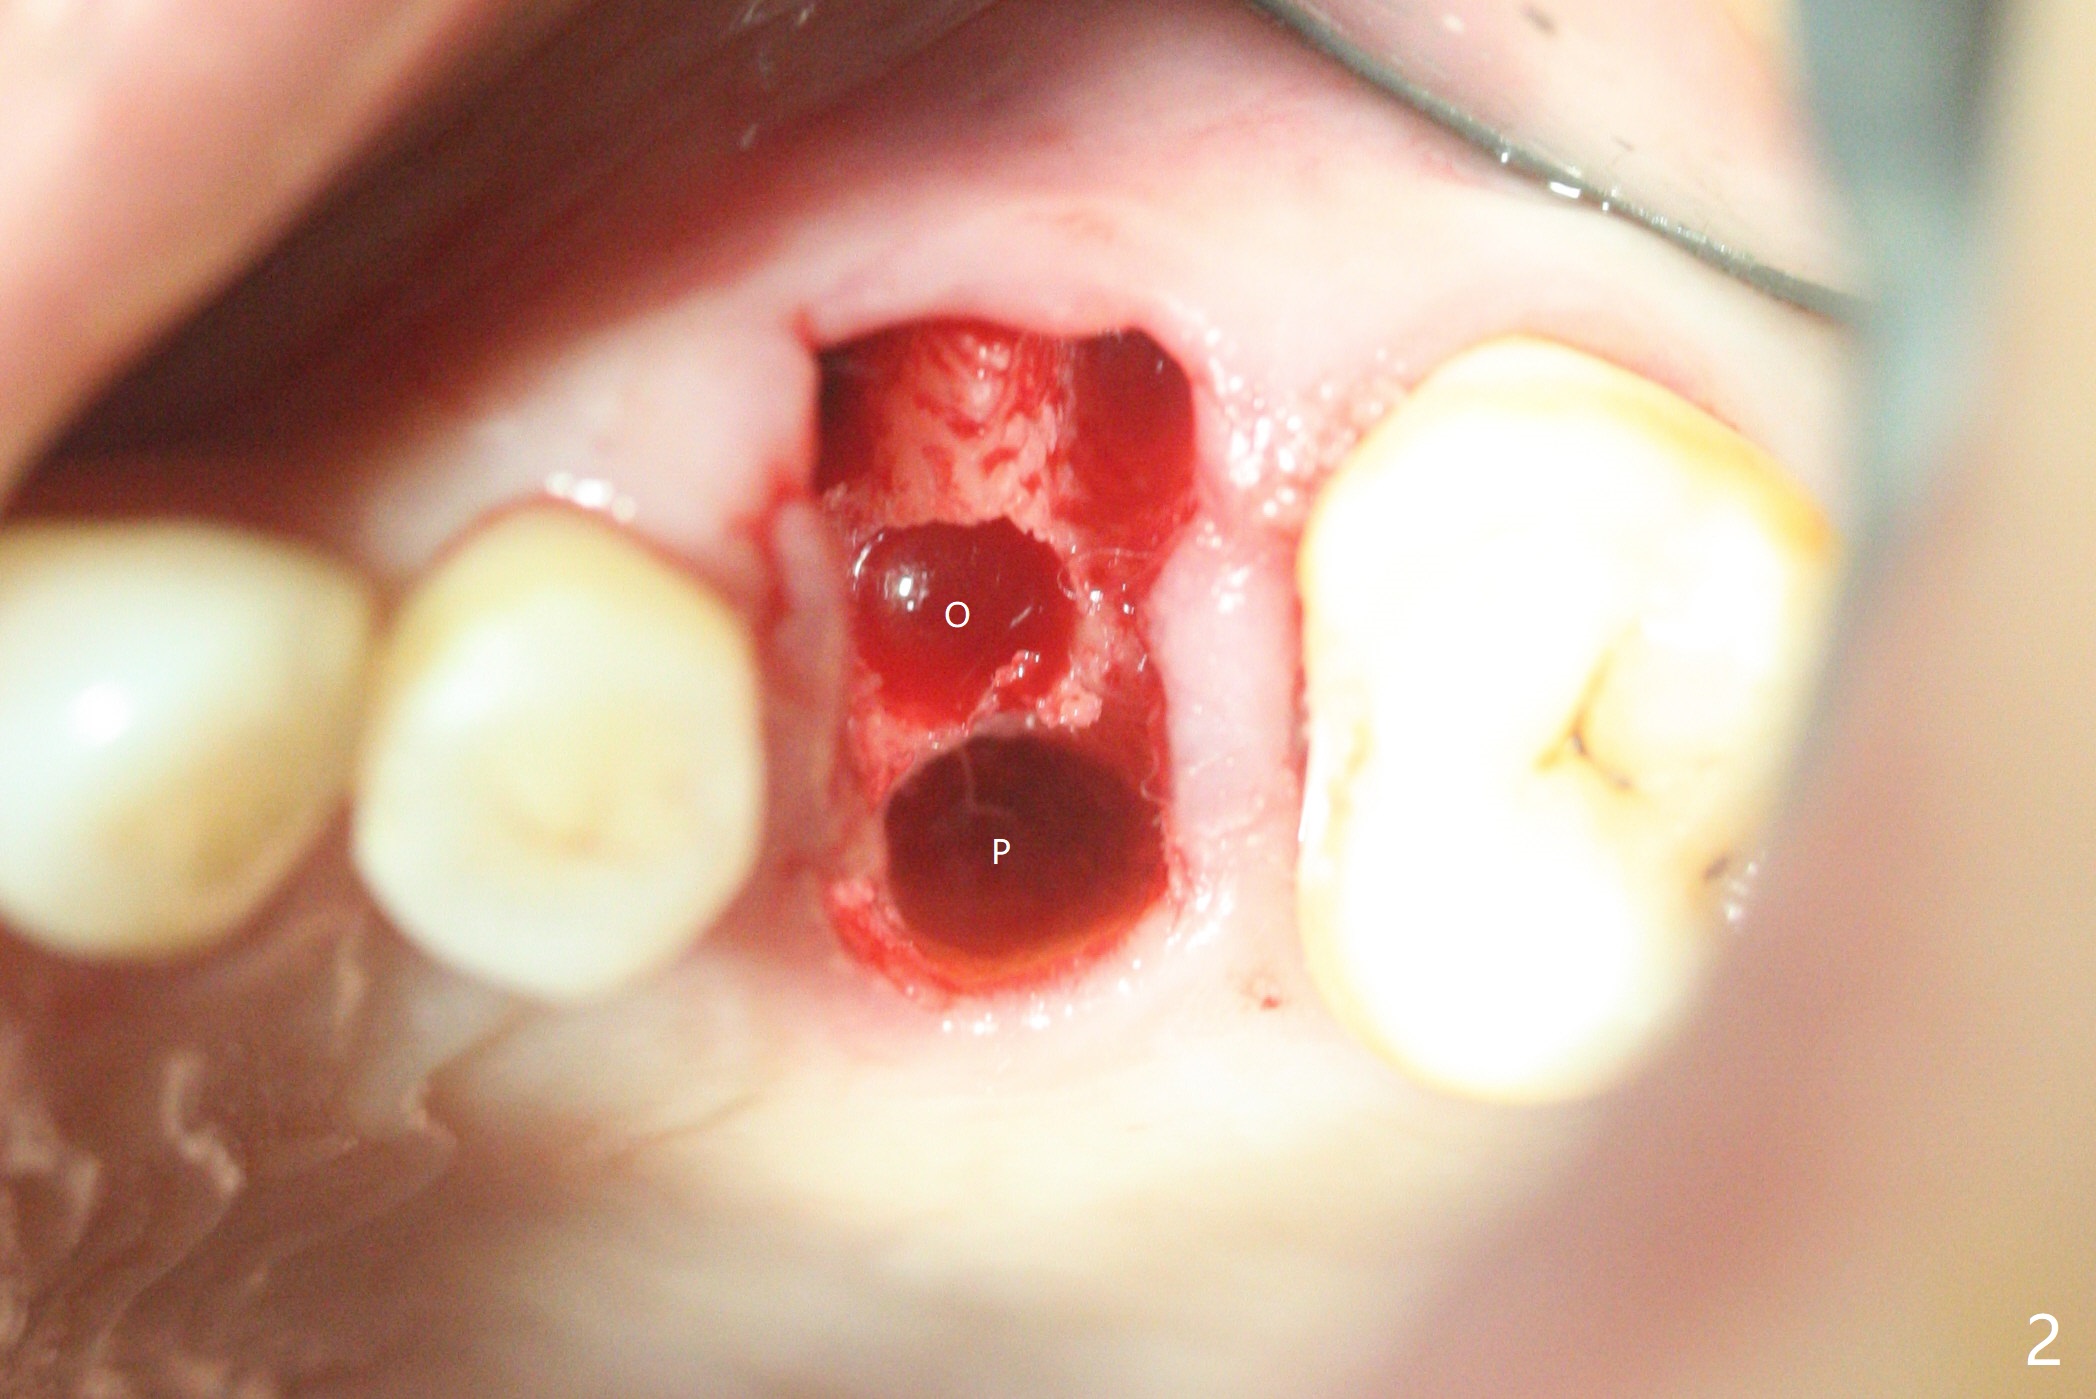

虽然没有保留左上6牙根,但是导板好像帮助钻洞(O)正好位于中隔当中(图一,二)。使用4.5(不是4.0)x10毫米钻头后,粘性骨粉和报废植体完成上颌窦提升术(图三:S)。拔除第一磨牙后发现第二磨牙近中面龋齿,立刻进行保守修补(图三:箭头);两个磨牙之间还有骨质吸收(*)。放置正式植体(10Ncm)后(图四),三个牙槽窝填入骨粉,包括近中颊侧(MB)和远中颊侧(DB),这时磨牙间缺损初步填补(*),然后放置基台以及基台周围骨粉,进一步充填磨牙间缺失(图五:*)。术后临时牙冠脱落两次,病人自己放回去,术后一周取出牙冠,骨粉还在(图六),腭侧有单纯疱疹病变(图七:>),开抗病毒漱口水处方,然后使用临时粘固粉。术后7个月15号牙近中牙槽嵴增高大约1.4毫米(图八:空箭头,从近中最颈部树脂算起)。术后七个月临时牙冠一直使用,防止食物坎塞,有利于骨质再生。术后7个月基台在口内没有更动(术中手拧紧),牙冠口内粘固,少量粘固剂遗留(图八:^)。牙冠/基台取出,去除粘固剂,牙冠/基台就位,用扳手拧紧(30 Ncm),基台与植体仍保持完全接触(图九)。只要植体植入角度好,没有倒凹,牙冠/基台再次就位就没有问题。